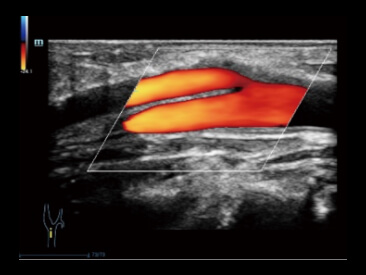

Une toute nouvelle maniû´re de dûˋmontrer le flux du

Doppler couleur 2D en visualisation 3D

Cas d'utilisation de Glazing Flow (mode puissance)?:

Arbre artûˋriel rûˋnal.

Le Glazing Flow permet une visualisation prûˋcise de la structure de l'artû´re arquûˋe et de l'artû´re interlobulaire mineure avec une vue en 3D.